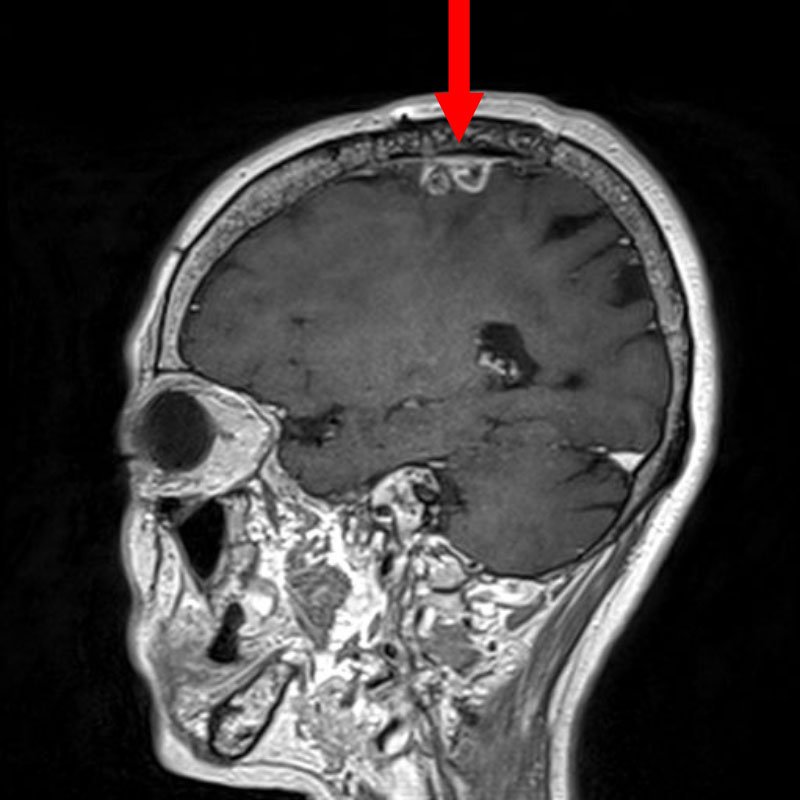

No.’25_108 手術前1

No.’25_108 手術前2